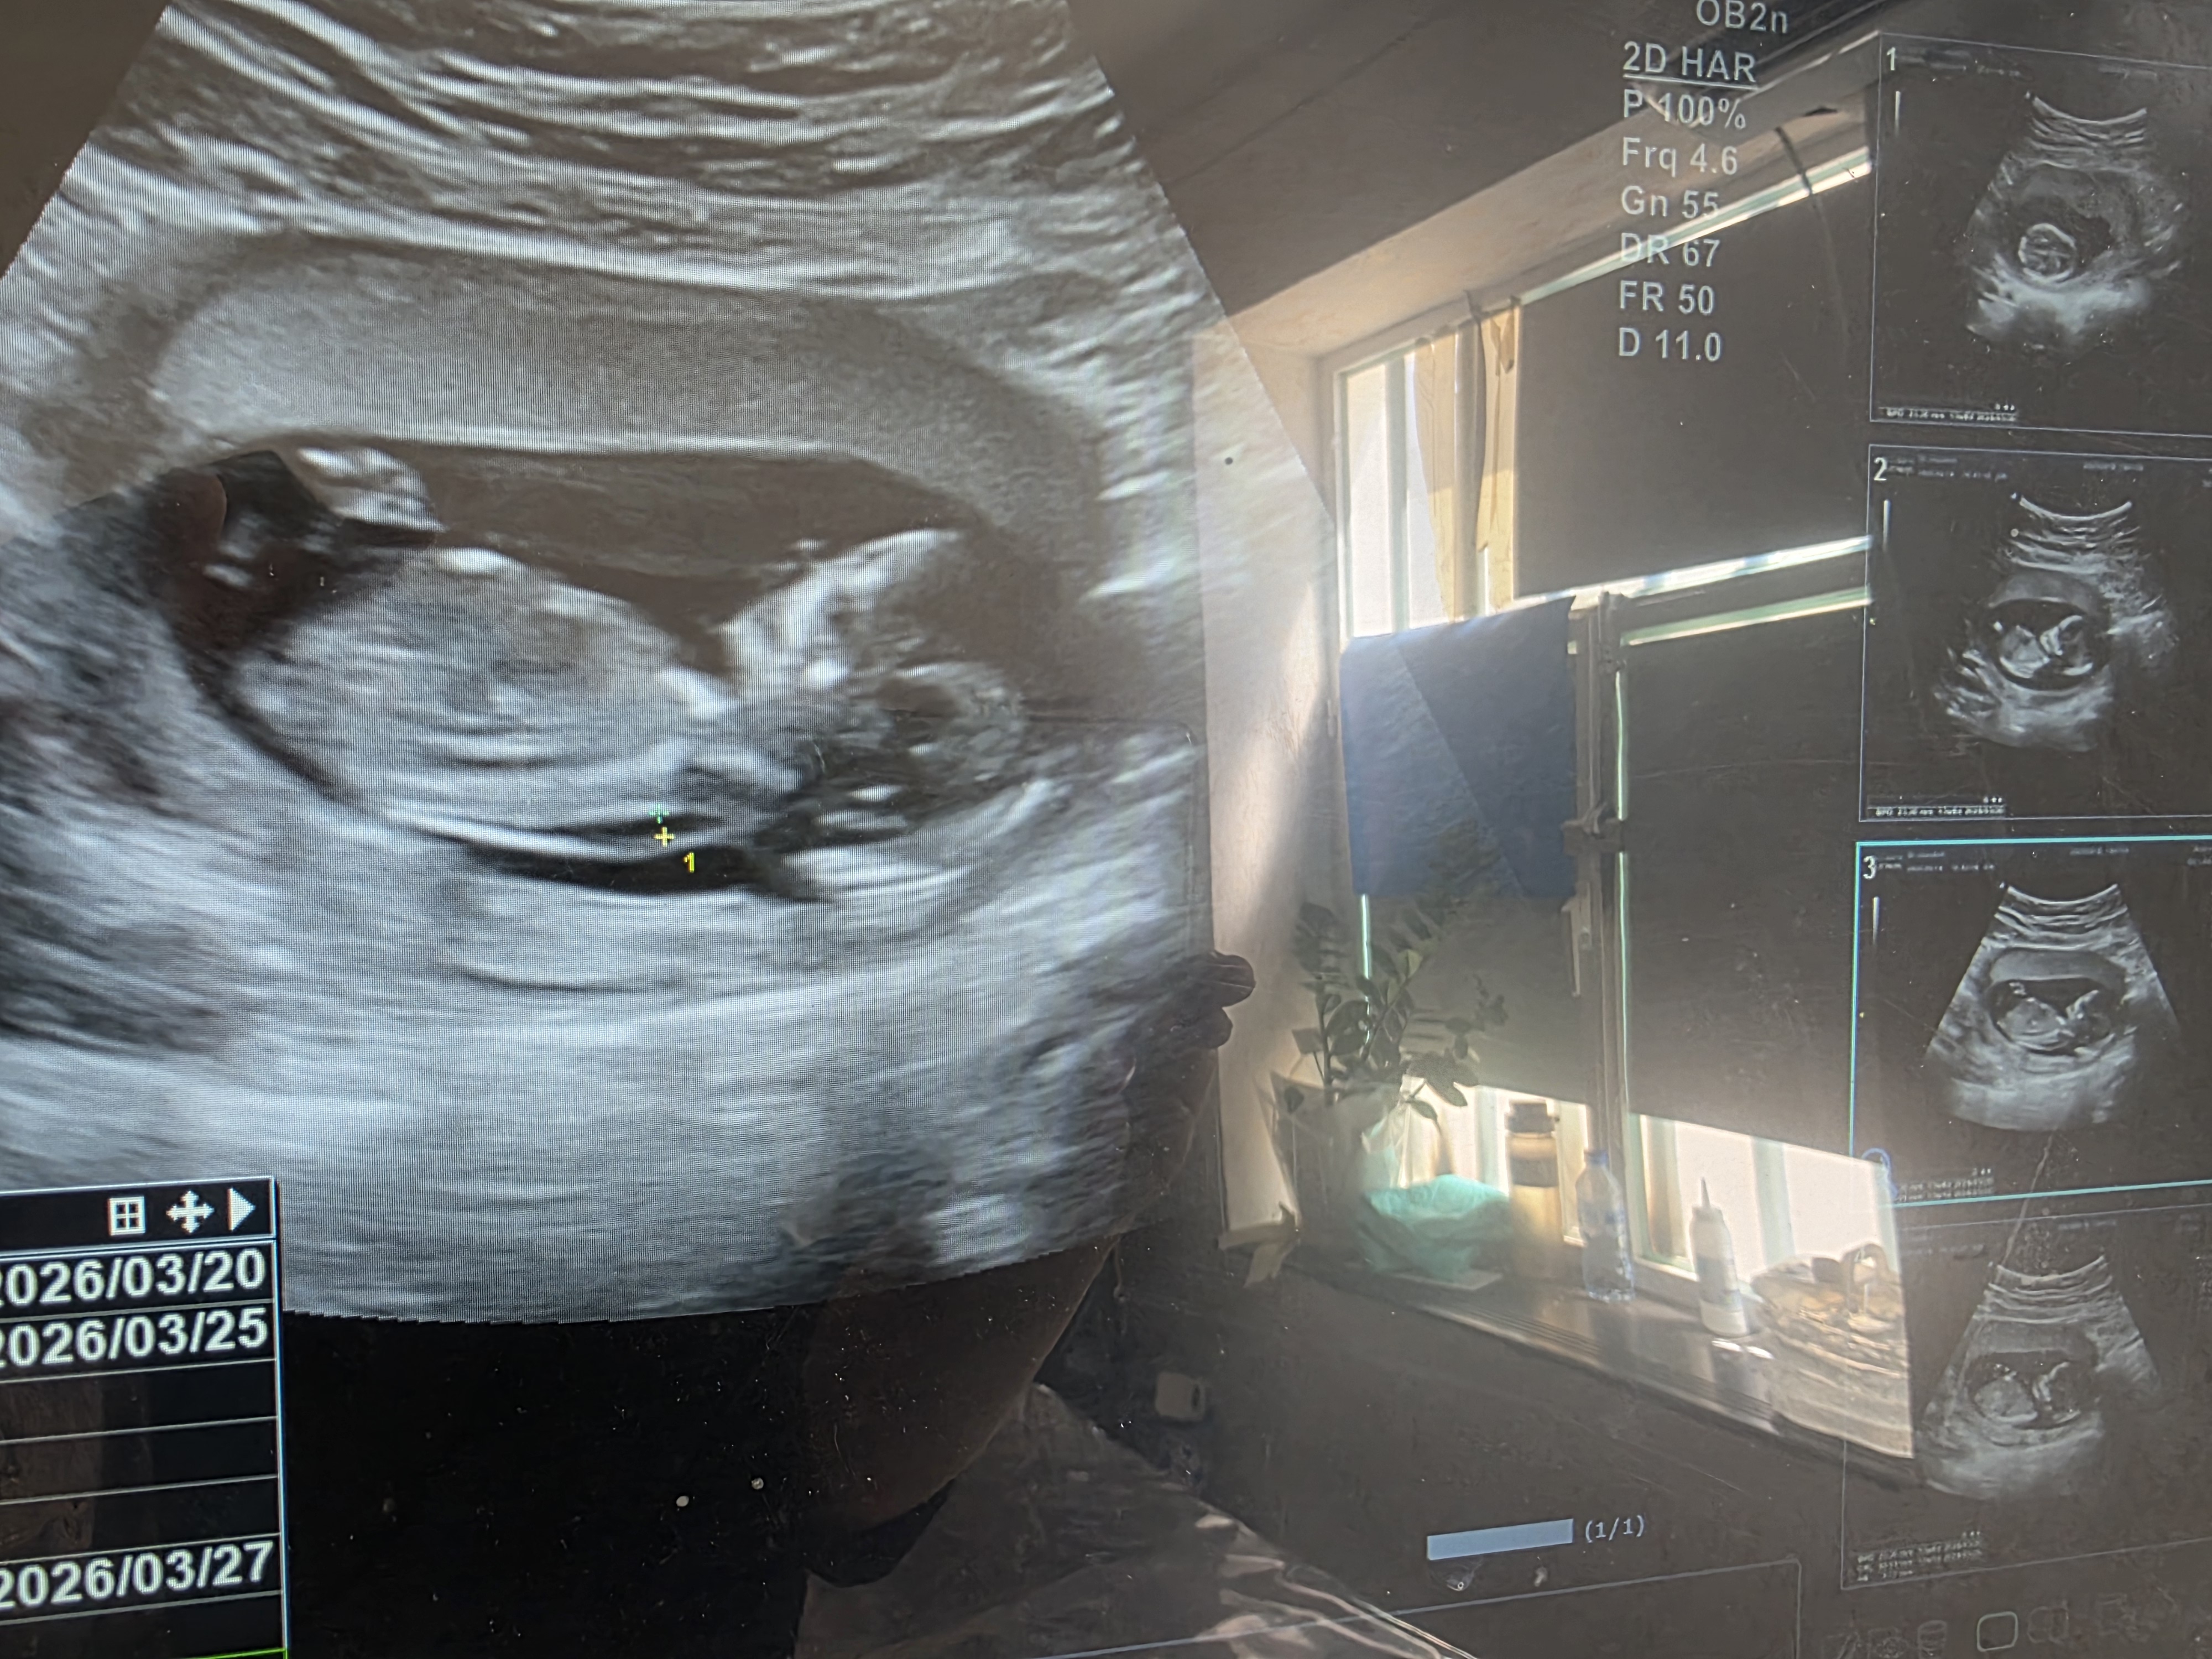

دخترخوب102938 مدیر استارتر عضویت: 1403/12/20 تعداد پست: 94 عنوان بیایید حدس بزنید بچم دختره یا پسر 71 بازدید | 6 پست 1404/07/18 | 10:44 0 نفر لایک کرده اند ... گزارش تاپیک نامناسب